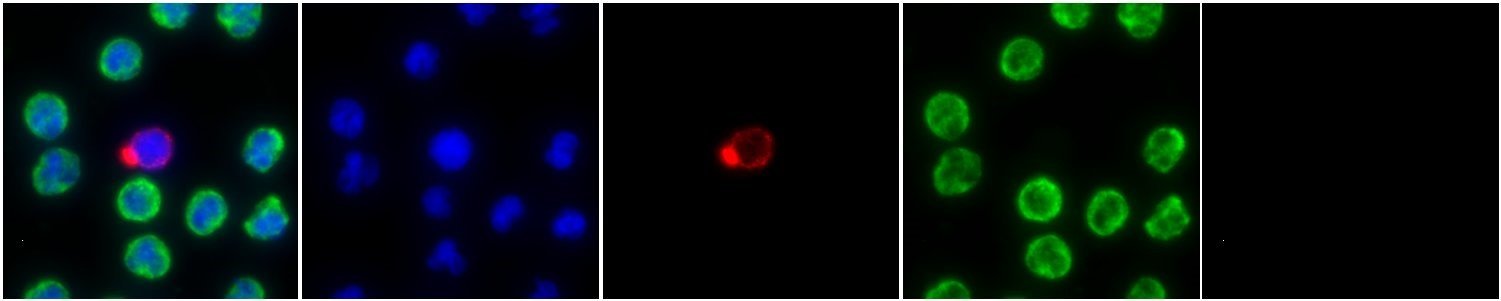

The presence of a single specific CTC phenotype (Cell Type K, shown left) was found to be predictive of resistance to both AR Tx and taxane chemotherapy. The KM curves below show the overall survival rate of patients with a prevalence of this CTC phenotype after they are given either standard of care drugs, AR Tx (HR=6.4) or taxane chemotherapy (HR=5.2).

Figure 7. Cell image of CTC subtype Cell Type K and KM curves of Cell Type K positive patients given either AR Tx or Taxane chemotherapy.